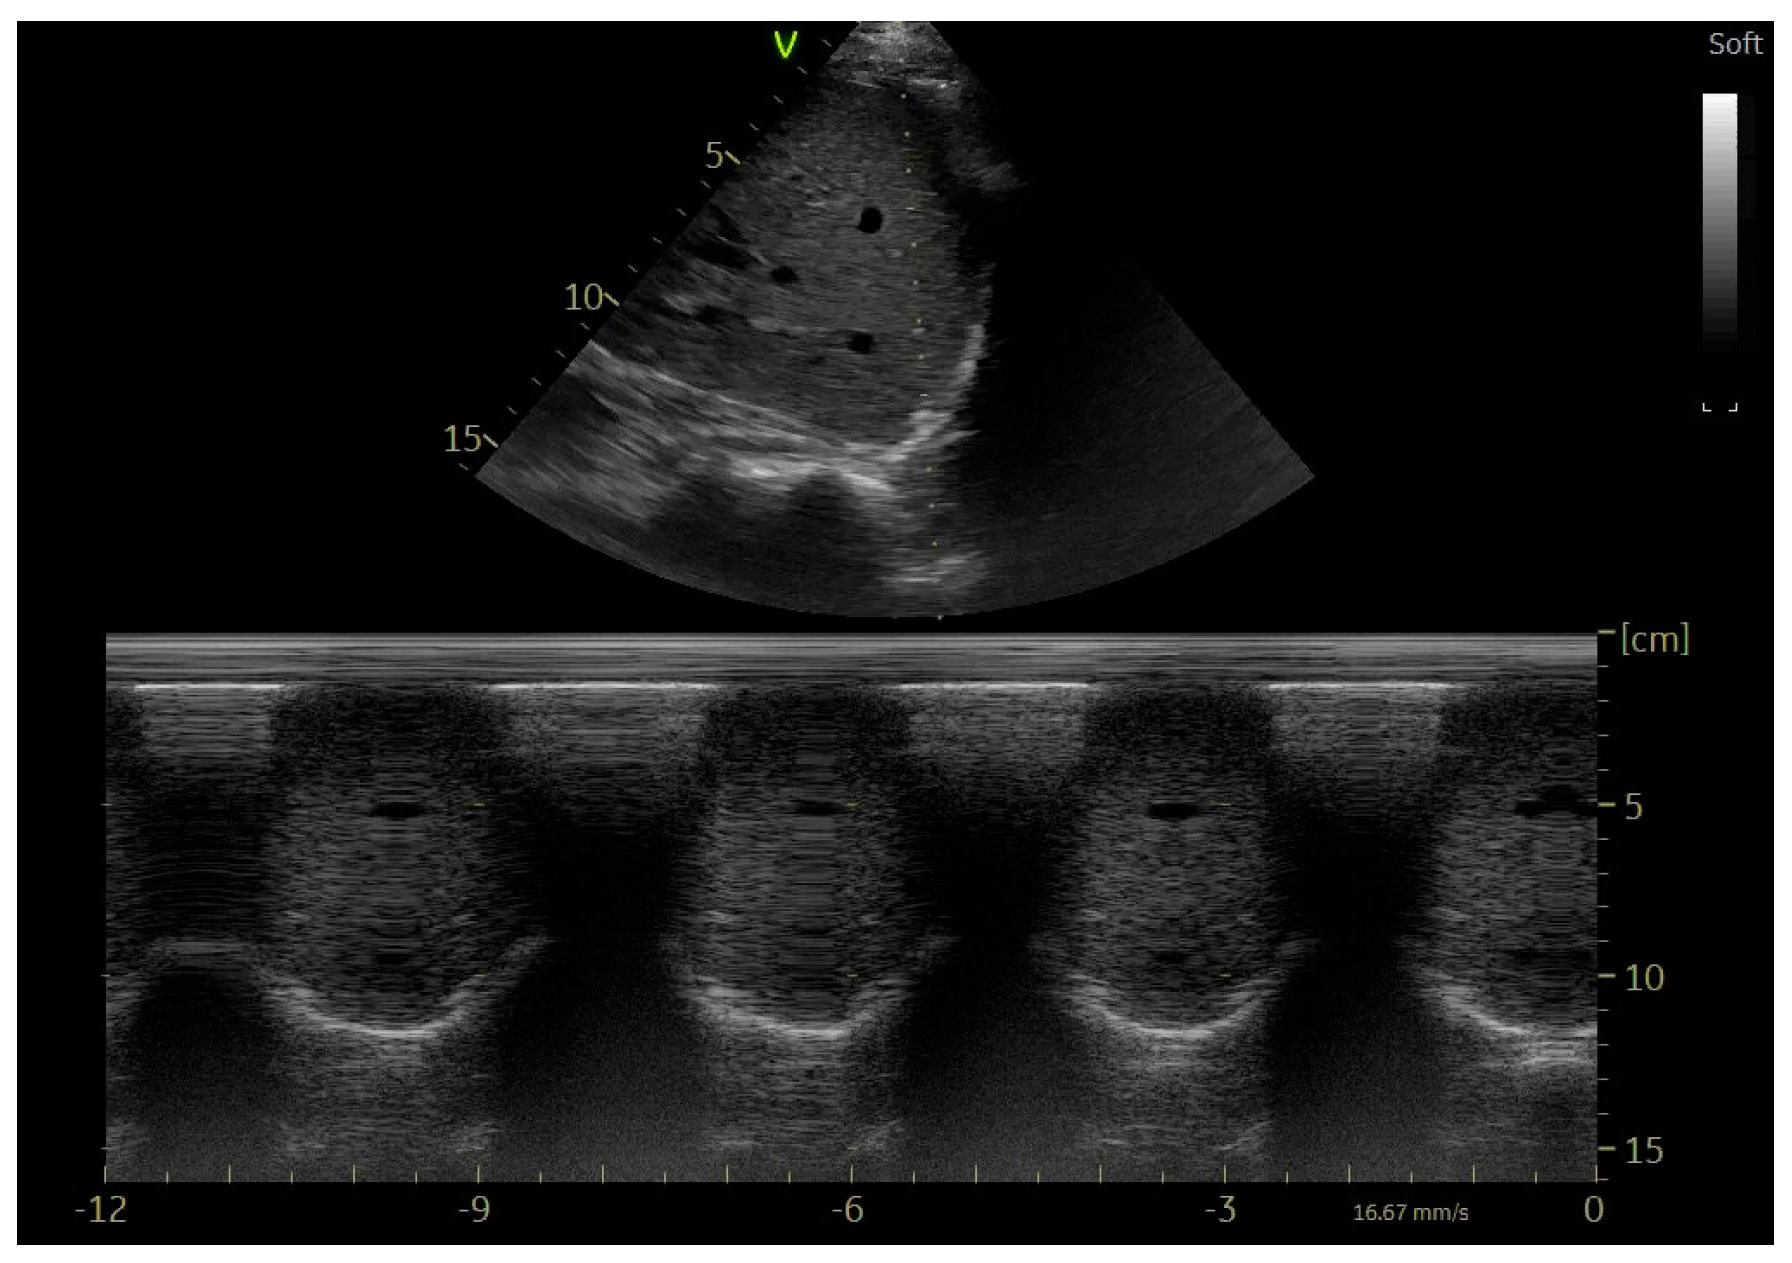

9. Echocardiographic Assessment of Diaphragmatic Function

10. Evaluation of the Diaphragm in Ventilated Patient